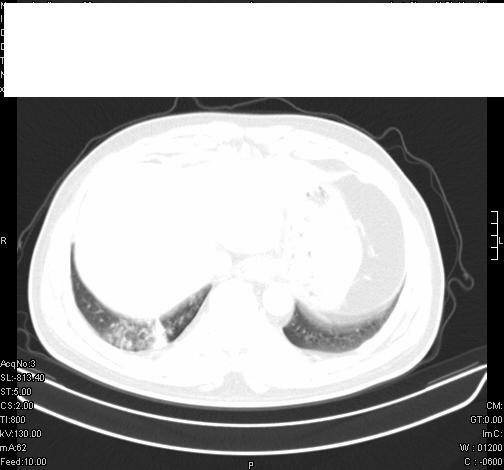

标题: CT6685:右肺阻塞性炎症,增强CT。

前几天,发了患者的平扫片,患者抗炎一周后增强扫描。右中叶病灶吸收明显,但下叶病灶未见明显吸收。右肺门可见结节影,看来凶多吉少

右肺下叶散在的斑片状致密影,下叶支气管变窄。考虑:右肺慢性炎症。

右下肺炎性改变

右肺下叶支气管壁不规则增厚,右肺下叶有斑片状影分布。考虑右肺中央型肺癌伴右肺下叶阻塞性改变。建议支纤镜检查。平扫比增强较好显示了病变情况。